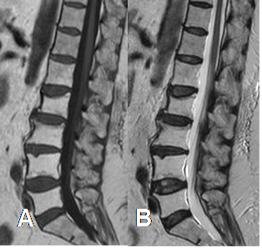

Fig 34 A. Cambios por radioterapia.

A: RM sagital en T1 y B: RM sagital en T2. Gran hiperintensidad en ambas secuencias de las vértebras L1 a L5, por conversión a MO grasa, secundaria a radioterapia.